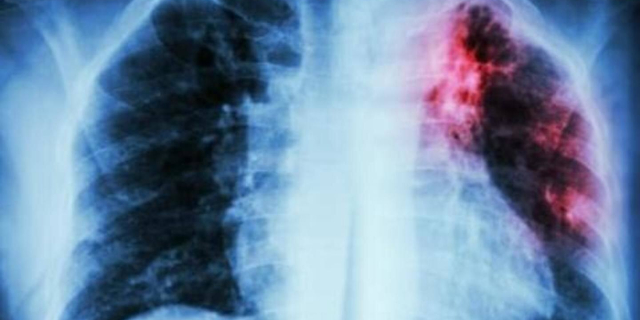

В республике сохраняется неблагополучная ситуация по туберкулёзу Больше всего заболевших - в Слободзейском и Каменском районах, а также Тирасполе 20 Мар., 2024, 11:51 Общество Туберкулёз Заболеваемость

С прошлого года наблюдается небольшой рост детской заболеваемости туберкулёзом Вместе с тем общее число выявленных случаев снизилось до 253 в 2022-м 01 Окт., 2023, 13:25 Общество Здравоохранение Туберкулёз

Заболеваемость туберкулезом в Приднестровье продолжает оставаться высокой В Минздраве сообщили, что нашли помещение для принудительного лечения пациентов с этим диагнозом 20 Апр., 2023, 11:08 Общество Туберкулёз Итоги года

В Рыбницком районе за год зафиксирован самый высокий показатель заболеваемости туберкулёзом Всего в Приднестровье в прошлом году заболевание впервые выявили у 253 человек 03 Мар., 2023, 09:45 Общество Минздрав Туберкулёз

За 9 месяцев 2022 года в Приднестровье выявили 408 случаев заболевания туберкулёзом Этот показатель несколько меньше по сравнению с прошлым годом 15 Ноя., 2022, 11:46 Общество Минздрав Туберкулёз

Количество заболевших туберкулёзом в Приднестровье ежегодно уменьшается на 5-8% Вместе с тем количество запущенных случаев заболевания растёт 18 Окт., 2022, 10:41 Общество Минздрав Туберкулёз